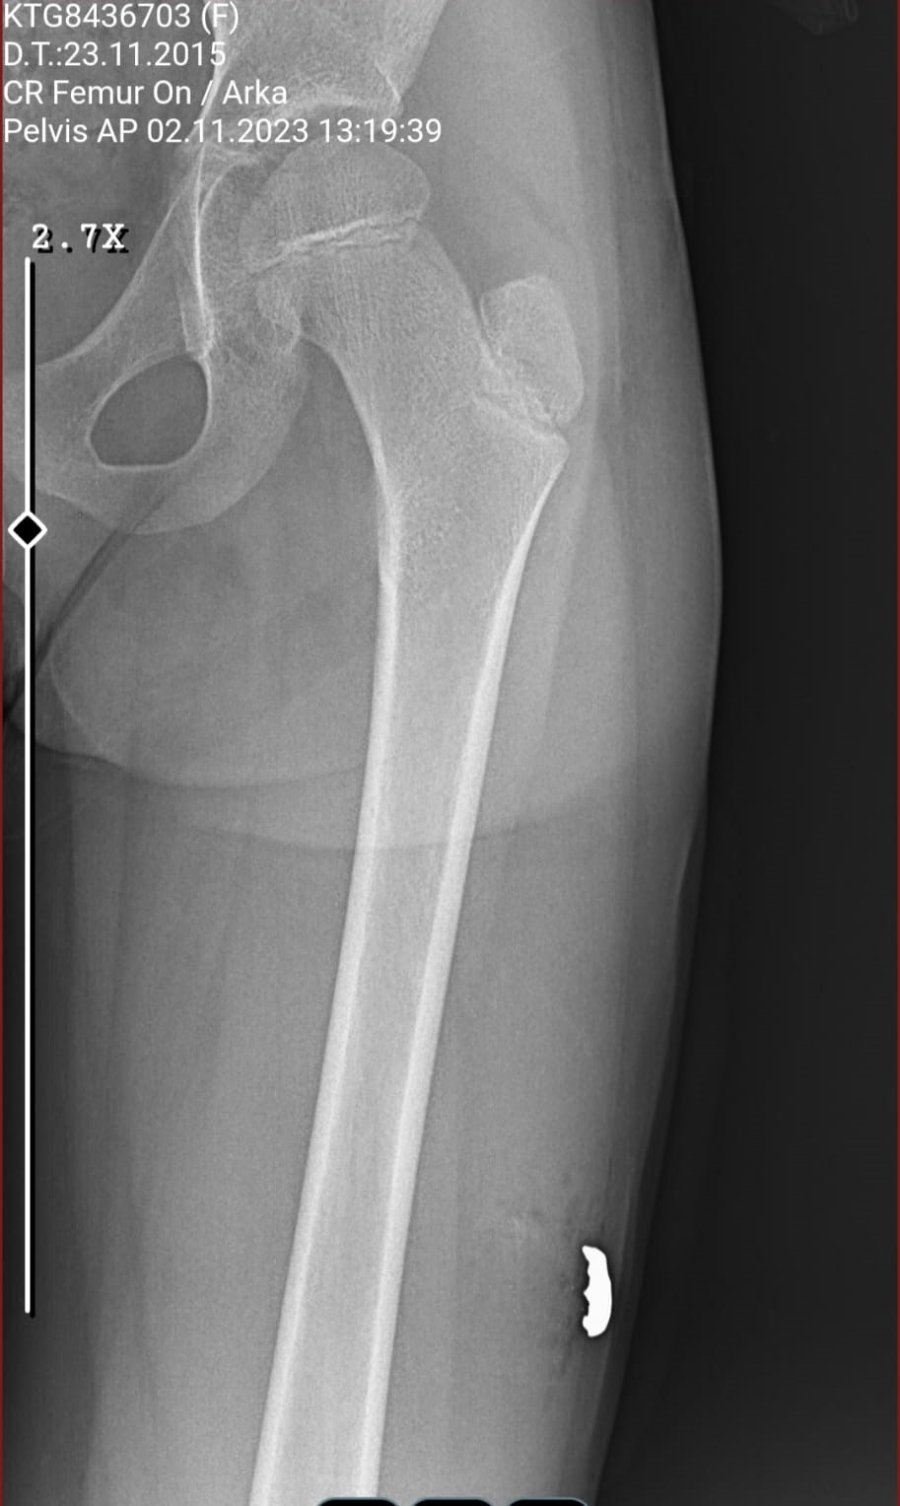

Kavgada hiçbir suçu yokken sol bacağına isabet eden kurşunla yaralanan 8 yaşındaki Sinem Uça ise Antalya Eğitim Araştırma Hastanesi'nde tedavi altına alındı. Burada operasyon geçiren Sinem'in baldır kısmından giren kurşun çıkartıldı. Yaklaşık 6 saatlik tedavinin ardından küçük kız taburcu olup evine gönderildi.

Kızını okula götürdüğü sırada kavgaya denk geldiklerini anlatan anne Şule Uça, evden dışarı çıktıkları esnada olayın gerçekleştiğini söyledi. Uça, "İki komşu arasındaki kavga, bizimle hiçbir alakası yok. Birbirlerine küfür ediyorlardı. Birden bire silah çıkarttı. Hemen çocuklarımı önüme aldım. Biz giderken silahı bize doğru doğrultup sıktı. Kızımın bacağına geldi. İlk başta hissetmedi, sonra "ayağım" deyince vurulduğunu anladık. Ya onun sıktığından sıçrayan kurşun ya da başka bir kurşun bilmiyorum. Yaralandıktan sonra ambulansa hastaneye götürdük. Kurşun içeride kalmış. Kurşunu çıkardılar ve 6-7 dikiş attılar" dedi.